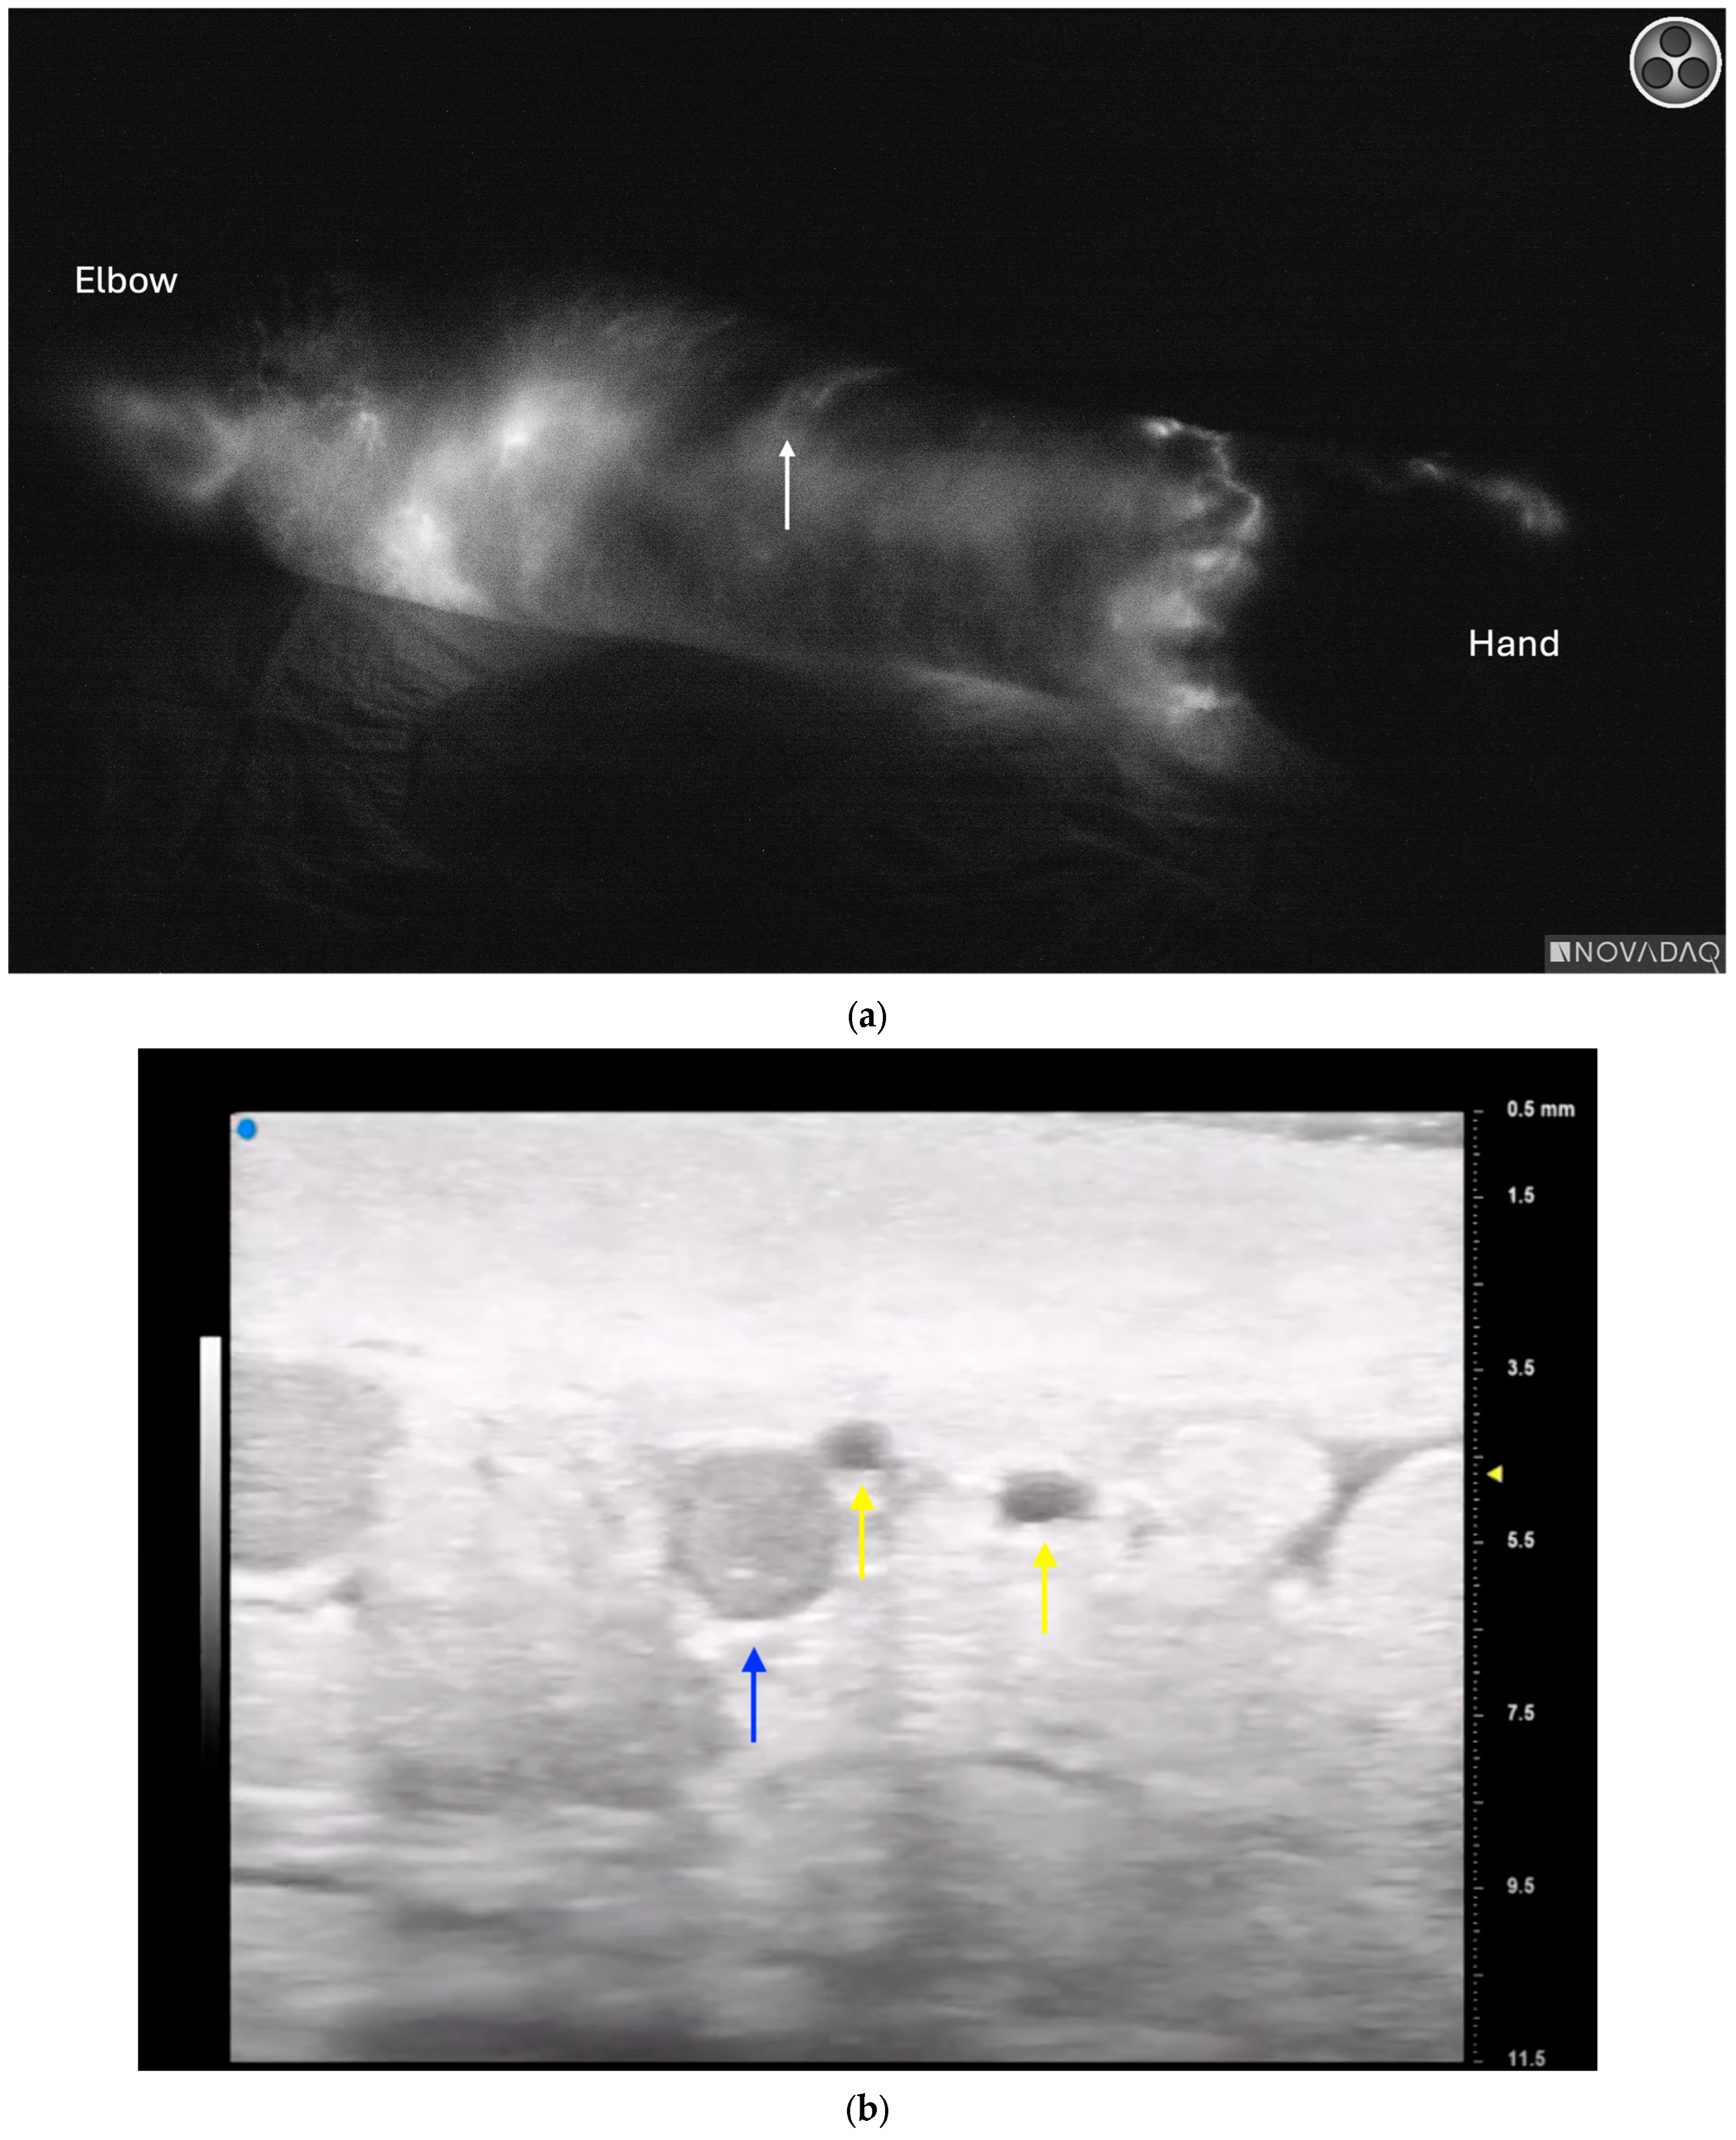

3.4. Lymphatic Surgery

- Hayashi, A.; Giacalone, G.; Yamamoto, T.; Belva, F.; Visconti, G.; Hayashi, N.; Handa, M.; Yoshimatsu, H.; Salgarello, M. Ultra High-frequency Ultrasonographic Imaging with 70 MHz Scanner for Visualization of the Lymphatic Vessels. Plast. Reconstr. Surg.-Glob. Open 2019, 7, e2086. [Google Scholar] [CrossRef] [PubMed]

- Hayashi, A.; Visconti, G.; Giacalone, G.; Hayashi, N.; Yoshimatsu, H. Recent Advances in Ultrasound Technology: Ultra-High Frequency Ultrasound for Reconstructive Supermicrosurgery. J. Reconstr. Microsurg. 2022, 38, 193–199. [Google Scholar] [CrossRef] [PubMed]

- Czedik-Eysenberg, M.; Steinbacher, J.; Obermayer, B.; Yoshimatsu, H.; Hara, H.; Mihara, M.; Tzou, C.J.; Meng, S. Exclusive use of ultrasound for locating optimal LVA sites—A descriptive data analysis. J. Surg. Oncol. 2019, 121, 51–56. [Google Scholar] [CrossRef] [PubMed]

- Seki, Y.; Kajikawa, A.; Yamamoto, T.; Takeuchi, T.; Terashima, T.; Kurogi, N. The dynamic-lymphaticovenular anastomosis method for breast cancer treatment-related lymphedema: Creation of functional lymphaticovenular anastomoses with use of preoperative dynamic ultrasonography. J. Plast. Reconstr. Aesthetic Surg. 2019, 72, 62–70. [Google Scholar] [CrossRef] [PubMed]